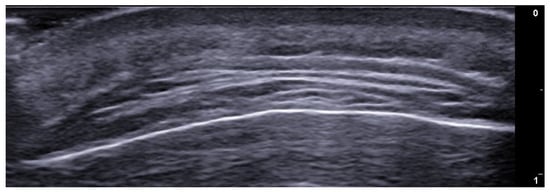

- Berritto, D.; Iacobellis, F.; Rossi, C.; Reginelli, A.; Cappabianca, S.; Grassi, R. Ultra high-frequency ultrasound: New capabilities for nail anatomy exploration. J. Dermatol. 2017, 44, 43–46. [Google Scholar] [CrossRef]

- Szymoniak-Lipska, M.; Polańska, A.; Jenerowicz, D.; Lipski, A.; Żaba, R.; Adamski, Z.; Dańczak-Pazdrowska, A. High-Frequency Ultrasonography and Evaporimetry in Non-invasive Evaluation of the Nail Unit. Front. Med. 2021, 8, 686470. [Google Scholar] [CrossRef]